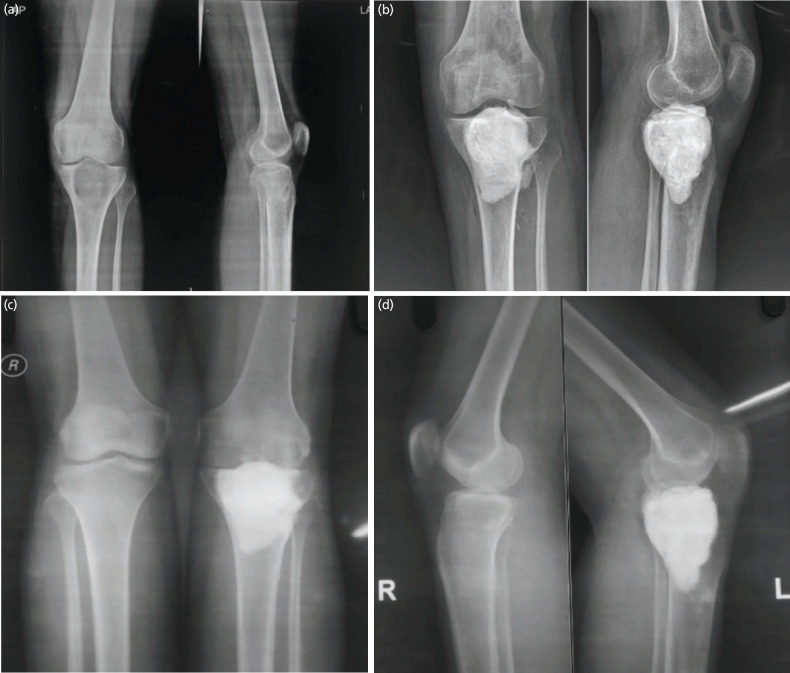

Material and methods: All patients with biopsy-proven GCT, involving either the distal femur or proximal tibia, and treated with either curettage with bone grafting (CBG), curettage with bone cementation (CBC), or curettage combined with grafting and cementation (the Sandwich technique) were included. They were further classified according to Campanacci grading. Patients were followed for a minimum of two years, and all complications were recorded.

Results: The three groups showed a statistically significant difference in terms of persistent pain after surgery (p=0.03), development of long-term arthritis (p=0.01), as well as overall complications (p=0.005). There was no significant difference in terms of the overall recurrence rate between each group (p>0.05). For Campanacci Grade II lesions, there was a statistically significant difference in terms of local recurrence (p=0.01), with lower recurrence rates observed after cementation procedures.

Conclusion: The study indicates that the Sandwich technique was associated with a lower rate of complications compared to CBG or CBC. Patients in the CBG group reported persistent pain, while those in the CBC group exhibited early arthritic changes within five years of the index surgery. Although there was no overall difference in recurrence rates, cementation procedures had a significantly lower rate of recurrence in Campanacci Grade II lesions.